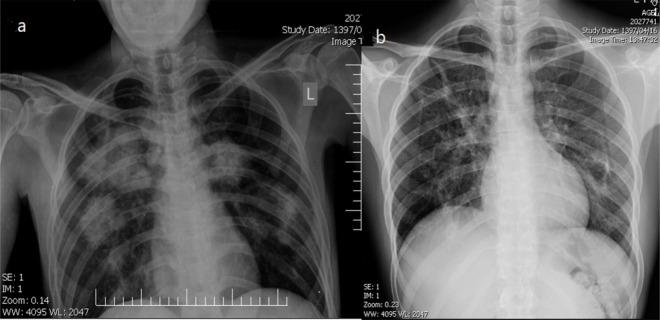

Chronic eosinophilic pneumonia (CEP) is a rare idiopathic interstitial lung disease, predominantly observed in females. Eosinophilia is present in most cases, and alveolar eosinophilia is a diagnostic criterion in more than 40% of bronchoalveolar lavage (BAL) samples. The current study reported a 27-year-old male patient, non-smoker, with a history of uncontrolled asthma, presented to the emergency room with a complaint of cough, fever, and moderate dyspnea. A 30% eosinophilia was reported in his peripheral blood sample. A chest-X ray examination showed an upper and middle lobe consolidation, especially in the left lung. Broad-spectrum antibiotics were then started with a presumptive diagnosis of pneumonia, but no improvements were evident. The chest computed tomography scan showed air space opacities with septal thickening and predominant involvement of upper and middle lobes. Flexible bronchoscopy was performed, and the BAL sample analysis showed eosinophil infiltration, while negative culture. No parasites were identified. Transbronchial biopsies demonstrated eosinophil accumulation in alveoli and interstitium.

慢性嗜酸性粒细胞性肺炎(CEP)是一种罕见的特发性间质性肺疾病,主要见于女性。大多数病例存在嗜酸性粒细胞增多,且在超过40%的支气管肺泡灌洗(BAL)样本中,肺泡嗜酸性粒细胞增多是一项诊断标准。本研究报告了一名27岁男性患者,不吸烟,有哮喘控制不佳病史,因咳嗽、发热和中度呼吸困难主诉就诊于急诊室。其外周血样本报告有30%的嗜酸性粒细胞增多。胸部X线检查显示上叶和中叶实变,尤其是左肺。随后开始使用广谱抗生素,初步诊断为肺炎,但未见明显改善。胸部计算机断层扫描显示气腔混浊伴间隔增厚,以上叶和中叶受累为主。进行了可弯曲支气管镜检查,BAL样本分析显示嗜酸性粒细胞浸润,而培养结果为阴性。未发现寄生虫。经支气管活检显示肺泡和间质中有嗜酸性粒细胞聚集。